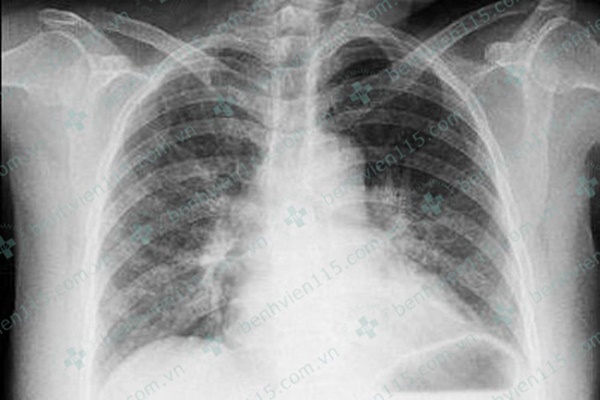

Ngày đầu nhập viện, bà B. có tình trạng suy tim cấp, phổi ran ẩm 2 phế (phế quản 2 bên phát ra âm thanh bất thường do bị co thắt, chèn ép) trường được xử trí theo phác đồ nhồi máu cơ tim cấp với thuốc đặc trị theo phác đồ nhồi máu cơ tim.